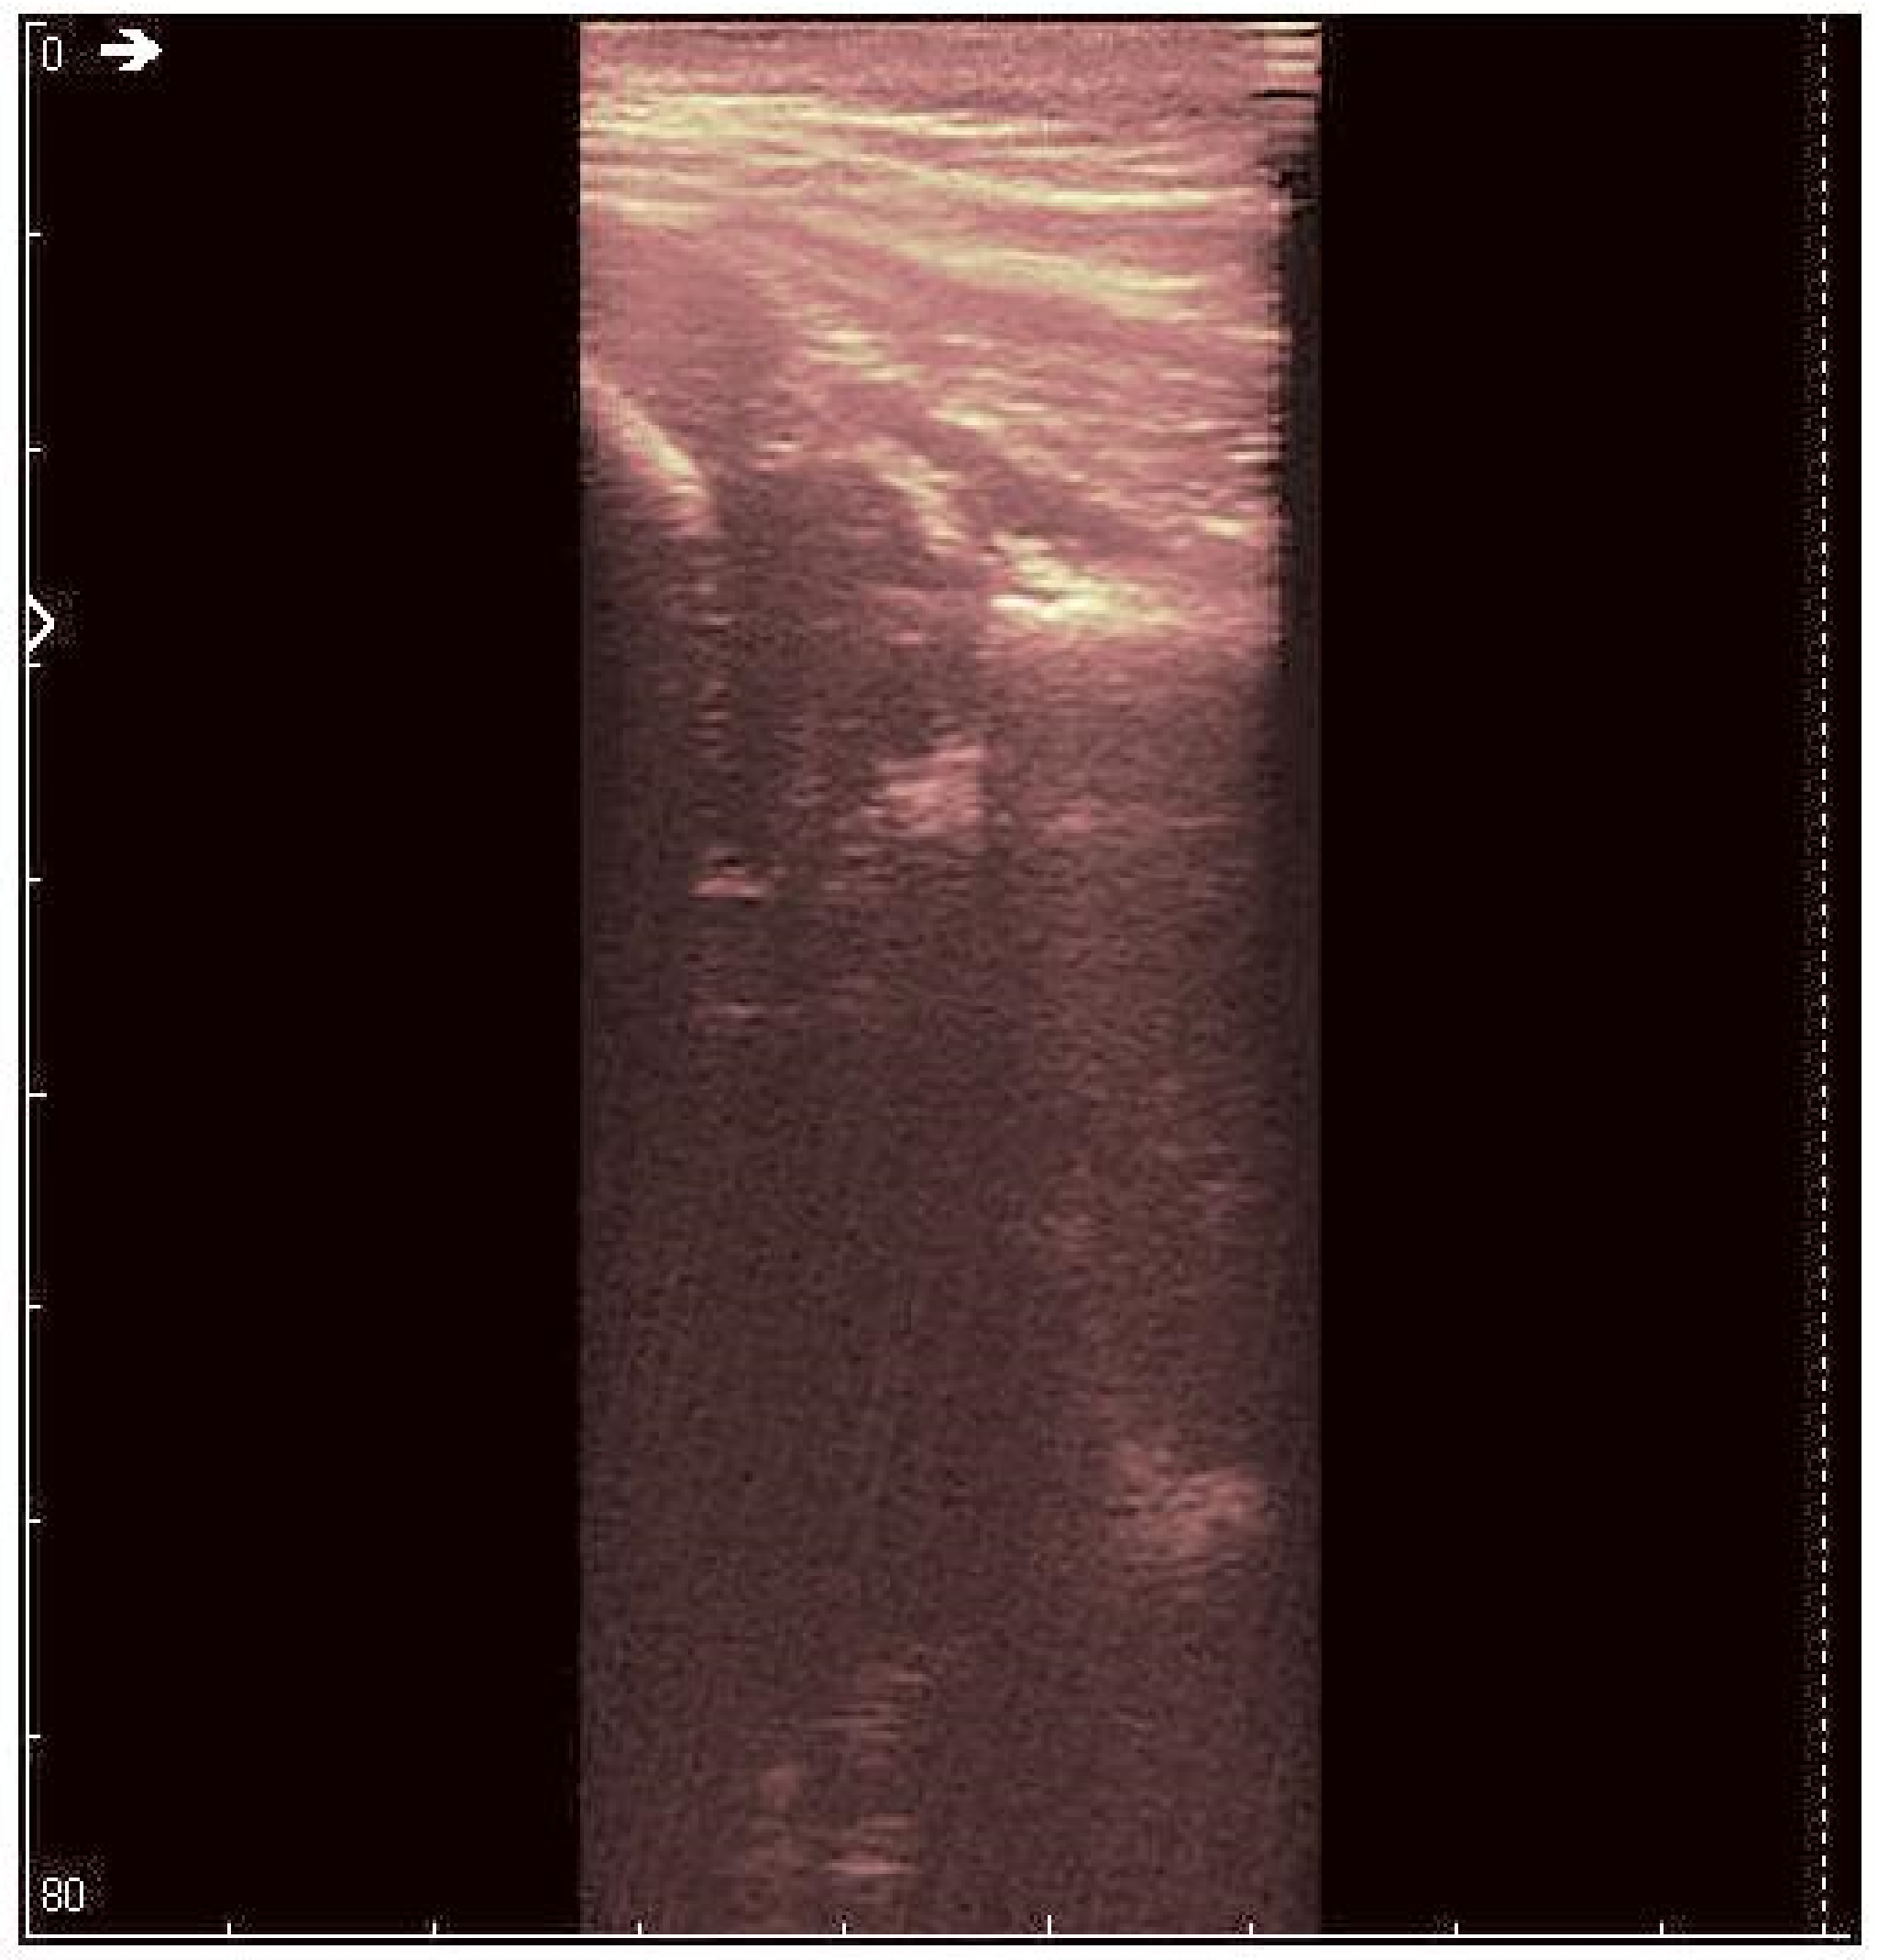

Neonates are prone to affections, which typically do not produce visible effects while the infants are less than one year old, due to their reduced movements. Hip dysplasia is one of the most occurring affections [1]. Developmental hip dysplasia (also known as congenital dislocation of the hip) is an abnormality of the hip joint—the articulation between the head of the femur and the acetabulum of the pelvis. It results in an increased risk for joint dislocation, as the socket portion (acetabulum) does not fully cover the ball portion (head of the femur), as can be observed in Figure 1 [2] The incidence of this disease varies between 1.5–25/1000 live births [3]. It can occur at birth, or develop later during growth, and occasionally one leg may be shorter than the other [4], which would hinder the child’s natural growth. Usually, the anterior section of the acetabular cartilage is the most vulnerable to the tearing of the acetabula [5]. Without treatment, complications in neonates may occur, such as limping, arthritis, and low back pain [6]. Additionally, the elderly are prone to fractures of the thin neck, which attaches the femur to the shaft, mostly due to degenerative effects, such as those induced by osteoporosis [7].

Figure 1. Normal hip (a) and hip dysplasia (b) in neonates.